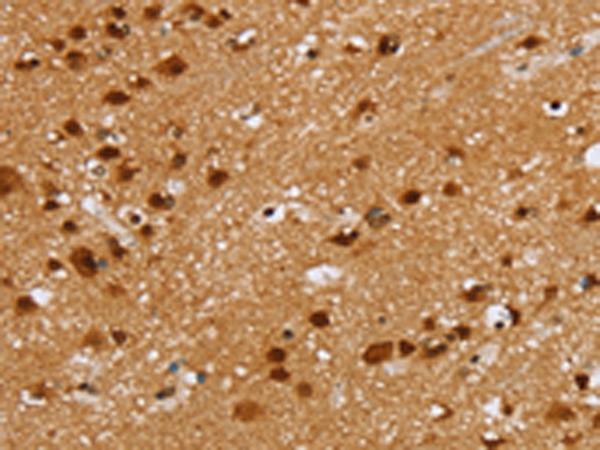

分类: 科研抗体货号: P08612别名: ABP32; PEF1A应用: WB,IHC反应种属: Human, Mouse, Rat